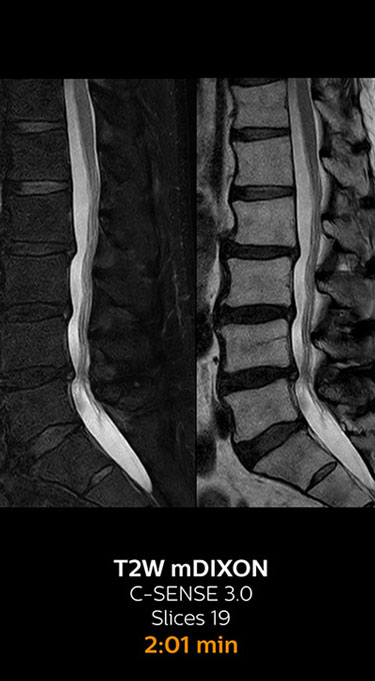

With Compressed SENSE, the scan time for the routine lumbar spine examination at KNC was reduced from 11:41 to 8:17 minutes,

MRI examination of the lumbar spine with Compressed SENSE

Ingenia 3.0T CX

Scan time 8:17 min. (was 11:41 min. without Compressed SENSE)